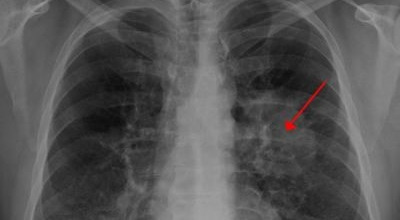

폐암 검사는 주로 X-ray를 통해 이루어지지만, 종양의 크기가 작거나 구석에 위치한 경우에는 확인이 어려운 경우도 있습니다. 그 후, 조직 검사를 통해 정확한 진단을 하게 됩니다. 폐암이 발견되면, 종양의 크기, 전이 여부, 위치에 따라 수술 여부를 결정하게 됩니다.